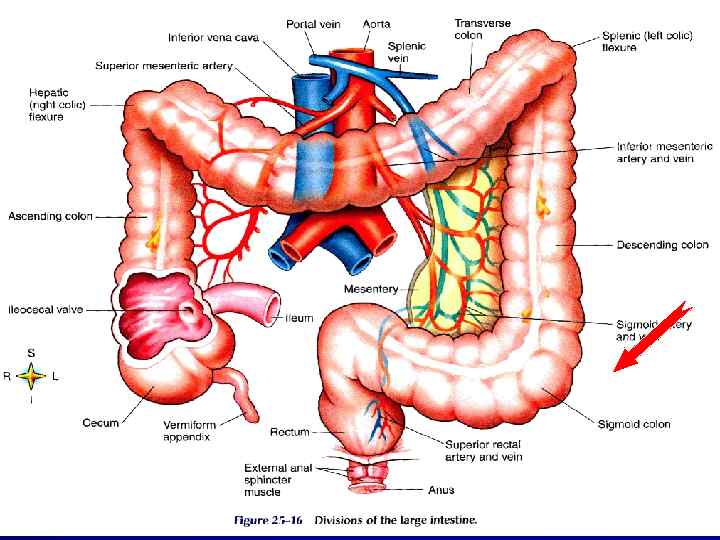

V МОТОРИКА ТОЛСТОЙ КИШКИ

V МОТОРИКА ТОЛСТОЙ КИШКИ

ФУНКЦИИ ВСАСЫВАНИЕ ВОДЫ И ЭЛЕКТРОЛИТОВ ХРАНЕНИЕ КАЛА t = 8 – 15 ч

ФУНКЦИИ ВСАСЫВАНИЕ ВОДЫ И ЭЛЕКТРОЛИТОВ ХРАНЕНИЕ КАЛА t = 8 – 15 ч

ИЛЕОЦЕКАЛЬНЫЙ КЛАПАН ЗАДЕРЖКА ХИМУСА СПОСОБСТВУЕТ ВСАСЫВАНИЮ В ТОЛСТУЮ КИШКУ ПРОХОДИТ ХИМУСА 1. 5 – 2. 0 л/сут

ИЛЕОЦЕКАЛЬНЫЙ КЛАПАН ЗАДЕРЖКА ХИМУСА СПОСОБСТВУЕТ ВСАСЫВАНИЮ В ТОЛСТУЮ КИШКУ ПРОХОДИТ ХИМУСА 1. 5 – 2. 0 л/сут

ДЕФЕКАЦИЯ КАЛ – гл. обр. в СИГМОВИДНОЙ КИШКЕ СЛАБЫЙ СФИНКТЕР и ОСТРЫЙ УГОЛ ПОПАДАНИЕ КАЛА в RECTUM → ПОЗЫВ КАЛ = 80 – 200 мл

ДЕФЕКАЦИЯ КАЛ – гл. обр. в СИГМОВИДНОЙ КИШКЕ СЛАБЫЙ СФИНКТЕР и ОСТРЫЙ УГОЛ ПОПАДАНИЕ КАЛА в RECTUM → ПОЗЫВ КАЛ = 80 – 200 мл

СФИНКТЕРЫ RECTUM ВНУТРЕННИЙ – ГЛАДКИЕ МЫШЦЫ НАРУЖНЫЙ – ПОПЕРЕЧНОПОЛОСАТЫЕ МЫШЦЫ (СРАМНОЙ НЕРВ)

СФИНКТЕРЫ RECTUM ВНУТРЕННИЙ – ГЛАДКИЕ МЫШЦЫ НАРУЖНЫЙ – ПОПЕРЕЧНОПОЛОСАТЫЕ МЫШЦЫ (СРАМНОЙ НЕРВ)